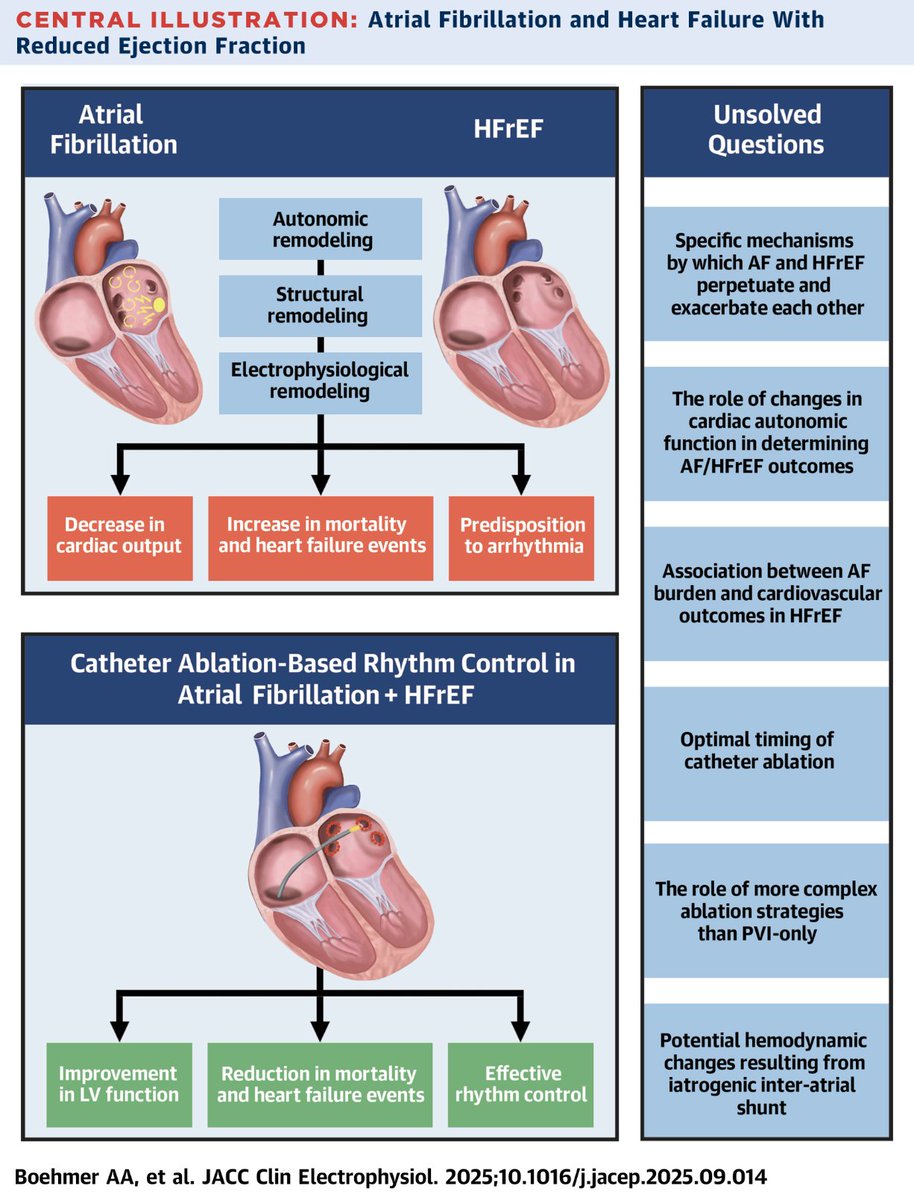

🔴Atrial Fibrillation & HFrEF: New Insights & Unresolved Questions @JACCJournals #Epeeps #Cardiology #CardioEd